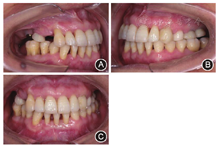

根分叉病变(furcation involvement,FI)3度,电活力测58,对照牙56。全口根尖X线片见图1,牙周检查表见图2。全口牙列不齐,上下前牙散在间隙,

间隙2 mm,

间隙3 mm。前牙Ⅱ度深覆

,Ⅰ度深覆盖,上颌中线左偏2 mm(图3),上下颌骨位置正常,面部对称。关节检查未见明显异常。